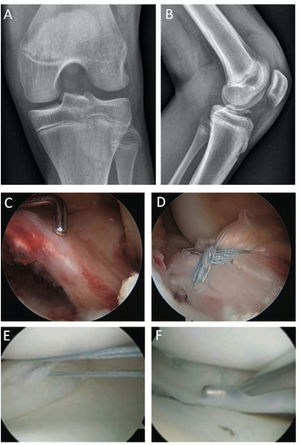

El estudio inicial se realiza con radiografías anteroposterior y lateral de rodillas. Estas pueden evidenciar la fractura avulsiva de la eminencia tibial en la mayoría de los casos, aunque fragmentos pequeños o puramente cartilaginosos pueden pasar desapercibidos30 (Figura 4).

Caso clínico avulsión de LCA y lesión meniscal concomitante. (A) Proyección AP y (B) Lateral de una fractura avulsiva de la espina tibial. (C) Visión artroscópica del mismo paciente que muestra la avulsión ósea de la inserción del ligamento cruzado anterior, que además compromete la raíz anterior del menisco lateral que se está incorporada en el fragmento óseo avulsionado. (B) reducción artroscópica y fijación con suturas de alta resistencia de la fractura avulsiva. (C) Rotura meniscal concomitante del cuerno posterior del menisco externo. (D) Reparación de lesión longitudinal del cuerno posterior del menisco lateral con dos suturas verticales con técnica todo-dentro.

Hoy en día, la RM es un elemento fundamental en la evaluación de estas lesiones, ya que permite: a) visualizar avulsiones puramente cartilaginosas, inadvertidas en las radiografías; b) cuantificar el desplazamiento y conminución del fragmento; c) reconocer lesiones intraarticulares concomitantes, meniscales o condrales, presentes en hasta un 37% de los casos y que requieren tratamiento31; d) identificar la interposición de partes blandas en el lecho de fractura (ej. cuerno anterior del menisco o ligamento intermeniscal) bloqueando la reducción del fragmento, lo que ocurre en un 29-48% de los casos32. Es por esto que la RM es parte del estudio de estas lesiones, y utilizamos la clasificación de Green & Tuca para graduarlas y definir su manejo33 (Figura 5).

En aquellas fracturas Grado II de Green & Tuca, se intenta una reducción cerrada. Si esta es satisfactoria, logrando un desplazamiento residual menor a 3mm, puede también realizarse un manejo conservador. De lo contario, si el desplazamiento residual es mayor a 3mm o es una FET Grado 3 de Green & Tuca, la indicación es la reducción quirúrgica y fijación29,33,35. El manejo quirúrgico de estas lesiones se realiza por vía artroscópica, y los objetivos son lograr una reducción anatómica de la fractura y una fijación estable que permita iniciar una rehabilitación precoz. Esta puede realizarse con tornillos o suturas, sin que haya clara superioridad de un método sobre el otro en la literatura actual36. Nuestra técnica de fijación preferida son las suturas, ya que, a diferencia de los tornillos, no requieren una segunda cirugía para su retiro (Figura 4).